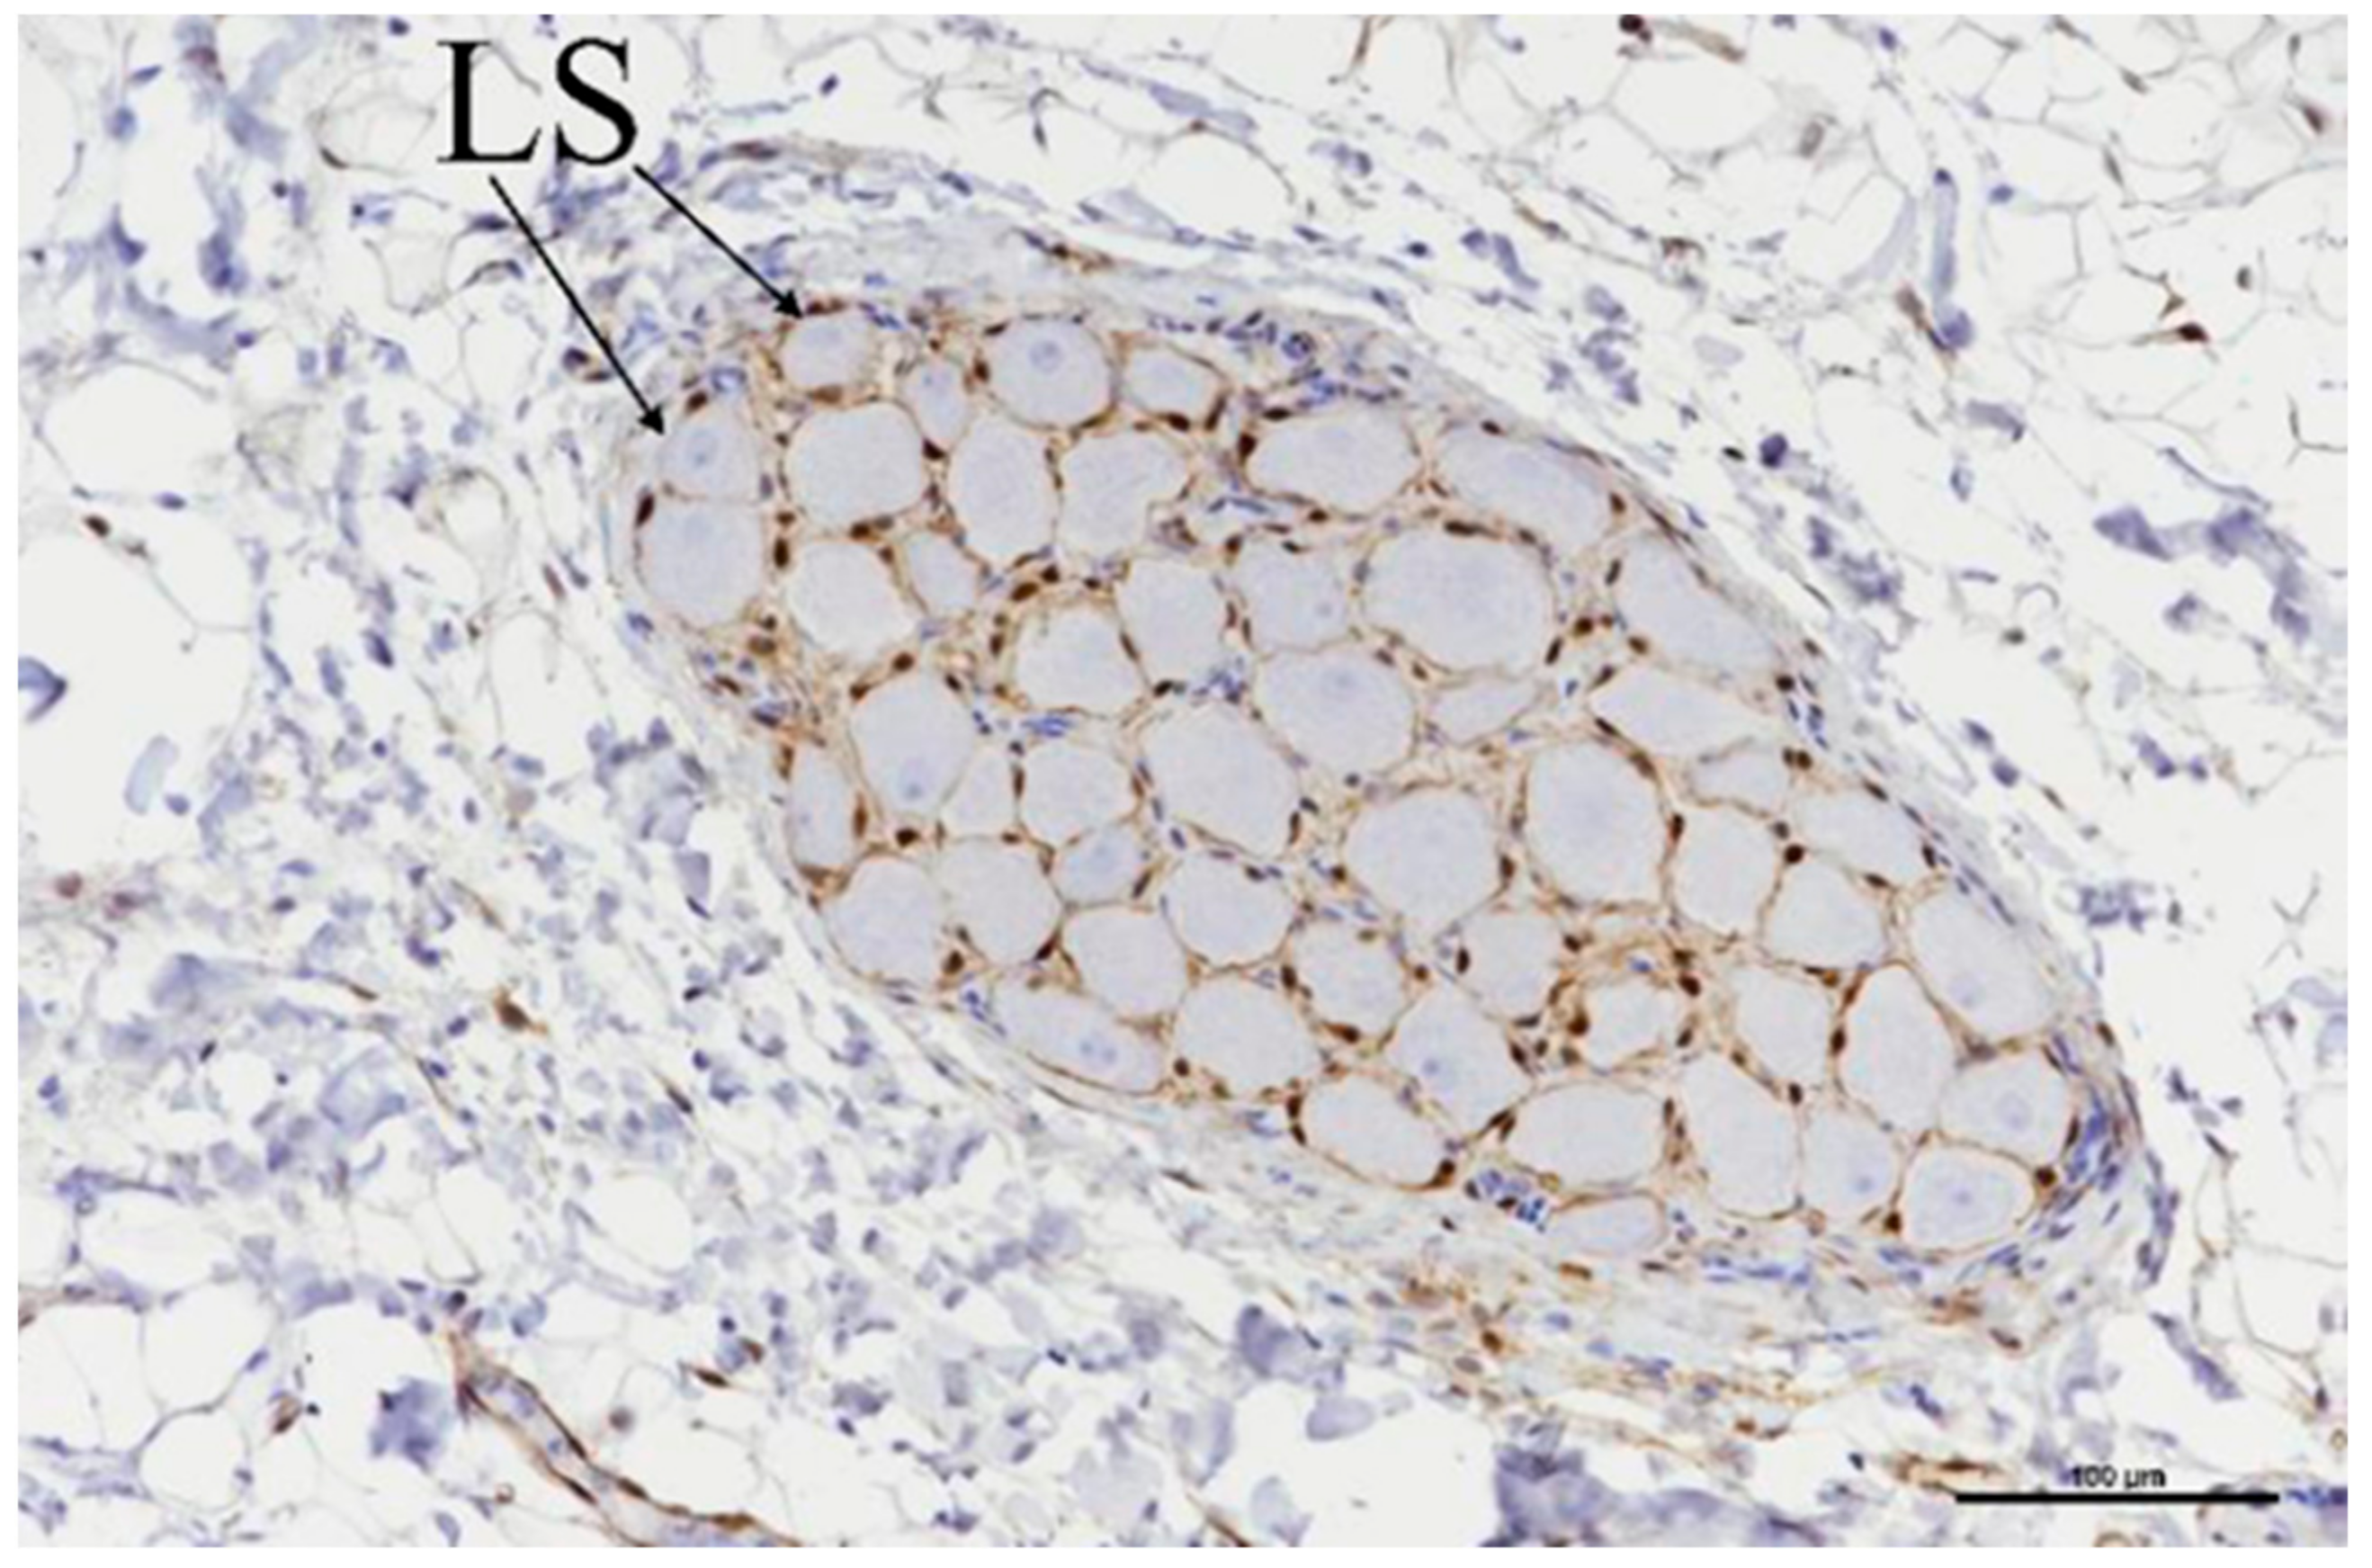

2.4. Histological Evaluation

3.3. Histologic Evaluation

3.4. Porcine Study—Catheter Access and Navigation